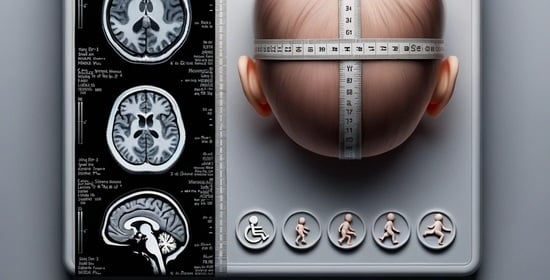

Predictors of Neurodevelopment in Microcephaly Associated with Congenital Zika Syndrome: A Prospective Study

:1. Introduction

2.2. Clinical Evaluation

| Radiological characteristics | |

| CT scan—infant age (in days) ‡ | 13 [3–68] |

| Evans’ index ‡ | 0.39 [0.35–0.44] |

| Ventriculomegaly | 39 (78) |

| Cerebral intraparenchymatous calcifications | 40 (80) |

| Neuronal migration disorders | 34 (68) |

| Cerebellum hypoplasia | 4 (8) |

| Corpus callosum anomaly | 20 (40) |